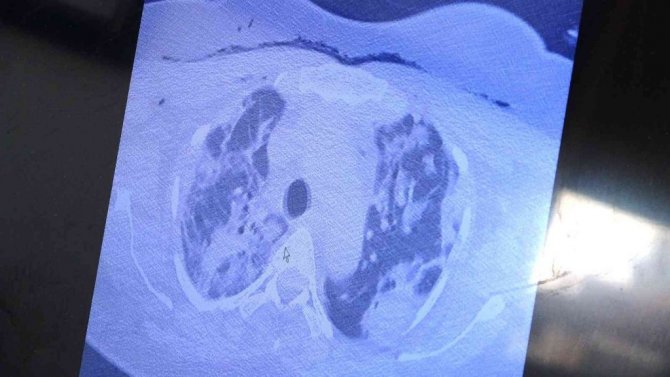

Yurt dışından kendisine gelen ve bebeği ile annesini hayata tutunmasını sağlayan Özkaya, "Bu yurt dışında hamileyken kovide yakalan ve ciddi akciğer tutulumu olan 38 yaşında hastamız var. Tedavi olmak için bizim ülkemize geldi. Ciddi solunum yetmezliği vardı. Biz hem annenin hem de bebeğin hayatını garanti altına almak için bebeği aldık. Sağlıkla doğum yaptı. Annenin akciğerine tomografi çektik. Ciddi akciğer tutulumu, ciddi harabiyet olduğunu tomografisinde gördük. Gecen yıllarda gebelerde böyle tutulumlar yoktu" ifadelerini kullandı.